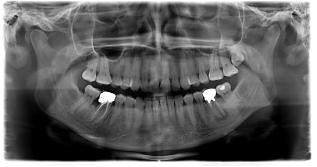

Ortopantomografia Digitale Standard

Ortopantomografia Digitale Rapporto 1:1